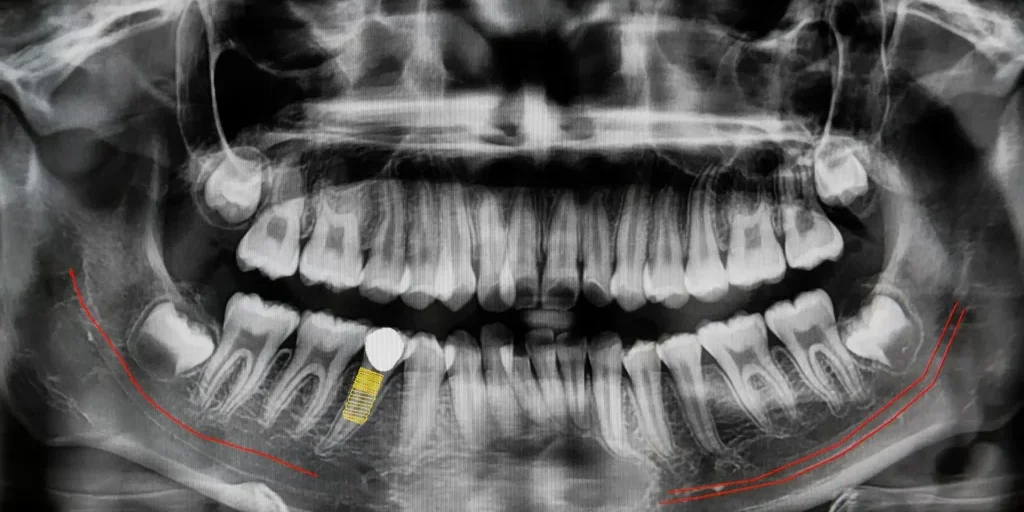

Le radiografie endorali o panoramiche sono esami diagnostici rapidi e indolori che permettono al dentista di “vedere” ciò che l’occhio nudo non può. Denti, radici, ossa mascellari, strutture invisibili durante una semplice visita clinica: tutto viene analizzato con precisione.

- Controllo dello stato delle otturazioni, corone o impianti, per verificare che tutto sia in ordine.

- Monitoraggio della salute ossea, essenziale soprattutto nei pazienti adulti o portatori di protesi.

- Valutazione di problematiche invisibili come infezioni, granulomi o cisti che non danno sintomi… finché non è troppo tardi.